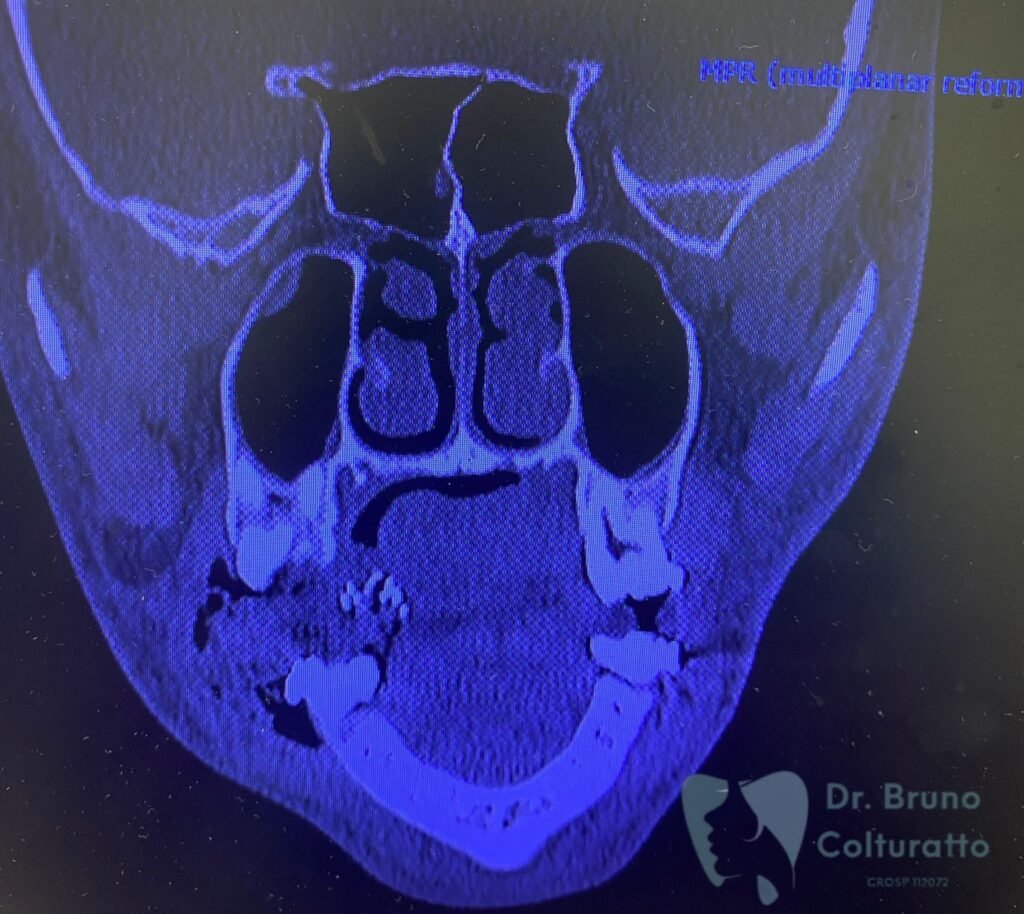

A Patologia Oral e Maxilofacial é a especialidade responsável pelo diagnóstico e tratamento de doenças que afetam a boca, mandíbula e estruturas faciais. Atua na identificação de lesões, cistos e tumores, garantindo diagnóstico preciso e tratamento adequado para preservar a saúde bucal e geral do paciente.